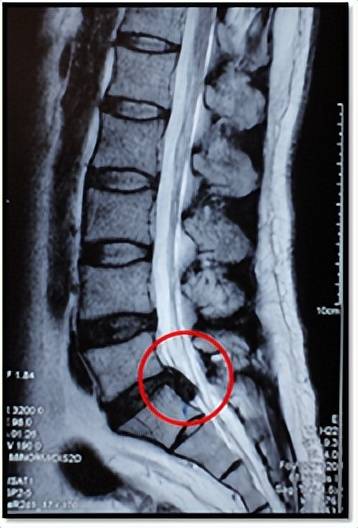

这是1例髓核游离脱出的病人,若是随便乱推拿,很有可能会压迫到脊髓及神经根加重原有的症状,甚至引起瘫痪。